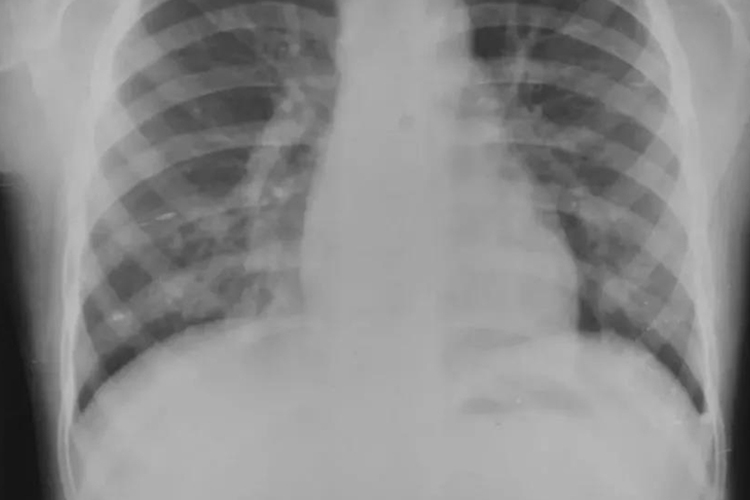

小叶肺炎是一种由细菌、病毒等病原体感染引起的肺部化脓性炎症,其病变特点是以细支气管为中心,向周围及纵深发展,最终影响所属的肺泡,形成以小叶为单位的灶状散布的肺化脓病灶。小叶肺炎常见于小儿、老年人及体弱多病者,尤其在冬春寒冷季节发病率较高。